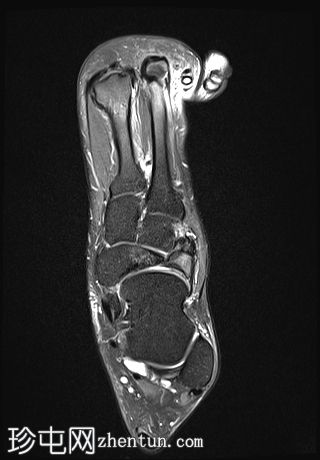

矢状面

PD 脂肪饱和度

7.jpg

T2

舟骨呈二分状,分为两个骨块——较大的内侧骨块和较小的外侧骨块。

内侧骨折块外侧面呈“逗号状”,舟骨相对于距骨头轻微向内移位。

外侧骨折块及其外侧均呈斑片状T1低信号和PD FS高信号,并伴有硬化和微小囊肿,提示软骨联合/纤维界面存在慢性应激反应或退行性改变,可能伴有缺血性坏死。

双分舟骨区域外未见急性骨折线或骨髓水肿。

周围跗骨和关节未见明显异常。

未见明显软组织异常或关节积液。